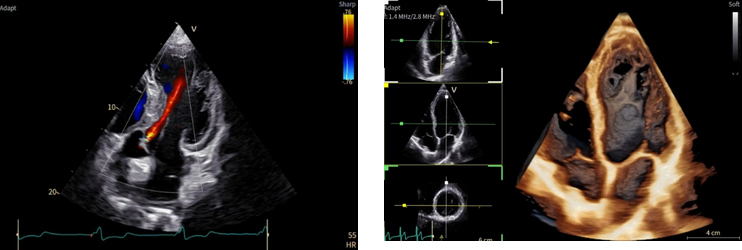

「Vivid Pioneer」は、これまで検査者が手作業で行っていた血流解析をAIが自動で行い、短時間で安定した測定プロセスを提供する。また、心臓の主要な部位(左心室と左心房)の動きや形を三次元で自動分析し、検査者間の標準化を支援する。そのほか、次世代の画像エンジン機能により、細部の見やすさ(空間分解能)や色の見やすさ(カラー感度)が向上し、より高精度な心臓の立体画像を描出する。

「Vivid Pioneer」は、精度・スピード・正確性が不可欠な心血管診断の要望に応えるために設計された。次世代の画像エンジン、AIによる自動化されたワークフローや計測、直感的なデザインを備えた「Vivid Pioneer」は、医療従事者が自信をもって迅速に高度化された心エコー検査を行えることを目指している。